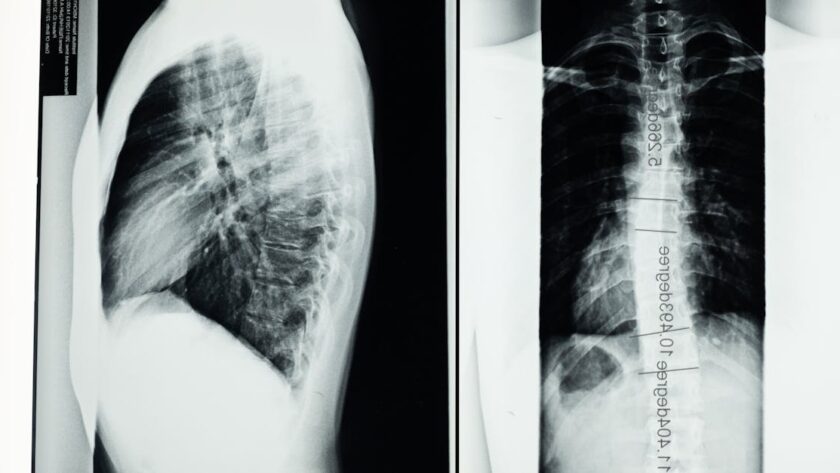

Le choix d’utiliser le Tildren cheval s’appuie sur la nature et la sévérité de la pathologie osseuse diagnostiquée. Chez un cheval montrant des signes de boiterie persistante, une inflammation osseuse localisée, ou des troubles articulaires à l’imagerie, le vétérinaire peut recommander ce traitement pour :

- Traiter l’arthrose : La prise en charge classique de l’arthrose vise à réduire l’inflammation et à protéger le cartilage. Le Tildren offre une action complémentaire qui limite la destruction osseuse associée et freine la progression de la maladie.

- Combattre l’ostéochondrose : Ce trouble du développement induit des lésions cartilagineuses et osseuses. Le Tildren agit ici pour moduler la dégradation osseuse et favorise la réparation.

- Réduire les effets de l’ostéite : En cas d’inflammation osseuse cheval, souvent très douloureuse, ce médicament aide à stabiliser la structure osseuse et à apaiser l’inflammation.

- Améliorer la consolidation après fracture : Chez les chevaux présentant des fractures ou micro-fractures, le Tildren peut renforcer la solidité osseuse et accélérer les soins osseux équins.